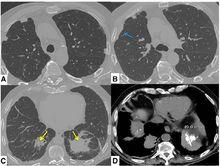

隱源性機化性肺炎2.2 CT的特點 :90%的COP患者CT表現為氣腔實變。將近50%的病例CT顯示病變沿胸膜下或支氣管周圍分布,以下肺區更明顯。當出現實變就能見到支氣管氣像。實變區常見輕度柱狀支氣管擴張。將近50%的病例常出現沿支氣管血管分布的小結節影。大約60%的病例出現磨玻璃影,通常與肺實質相伴隨。胸腔積液罕見,大多數COP患者經治療後影像學改善。然而未經治療時,一個部位的肺實質異常可能消散或擴大,甚至出現在新的部位。

2.3 影像學鑑別診斷: 呈現實變影的COP患者影像學鑑別診斷包括肺泡癌、淋巴瘤、血管炎、結節病和感染(尤其是結核或不典型的分枝桿菌感染)。但實變影位於胸膜下時,應考慮慢性嗜酸性粒細胞肺炎的診斷。表現為多發塊影的患者需要與肺部轉移瘤、淋巴瘤和肺部感染,如細菌性栓塞鑑別,多數情況下經支氣管肺活檢有助於排除上述疾病,具備相應的臨床表現。經抗生素治療數周,實變影仍然增長,CT顯示以支氣管周圍或胸膜下分布為主的實變影,高度提示COP。